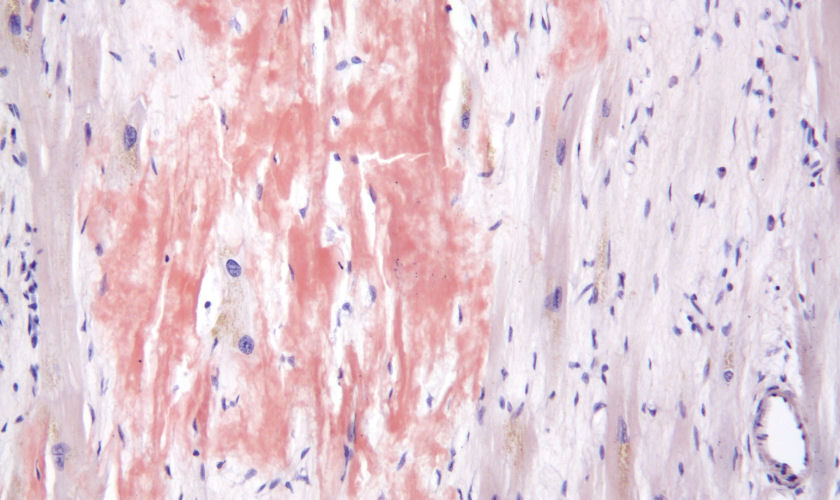

back cardiac amyloidosis

Source: Cardiac amyloidosis high mag.jpg